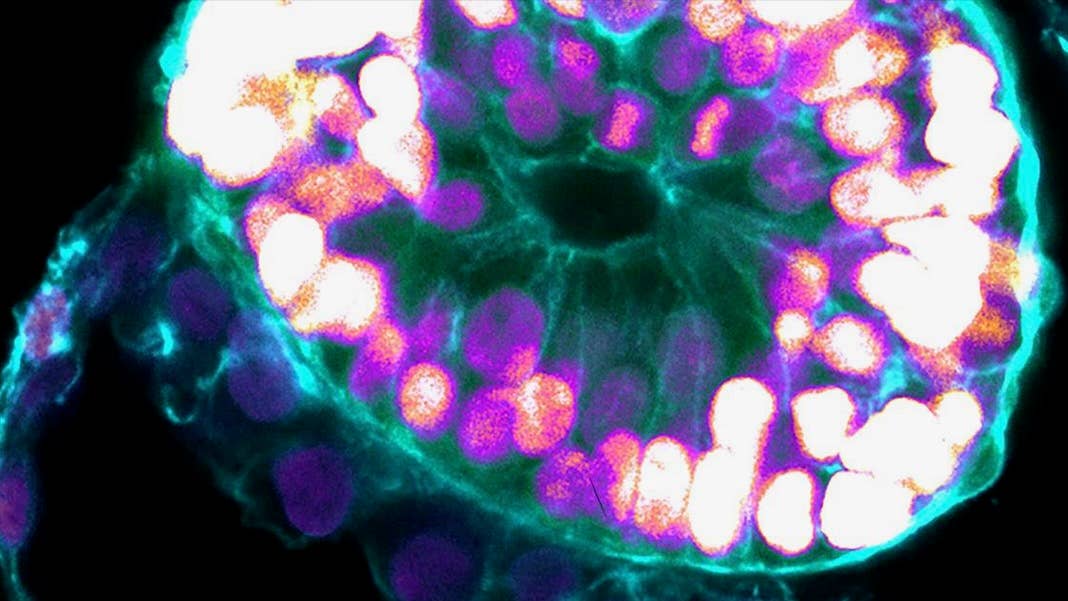

Using human stem cells, scientists have created human embryo-like structures inside petri dishes. These lab-grown blobs develop multiple structures that mimic a human embryo after implantation into the uterus—a major milestone for fertility—and last at least 14 days.

A new study published in Nature from embryoid veteran Dr. Jacob Hanna now pushes the lab-gestation timeline forward. The team turned human embryonic stem cells into embryoids that model early human embryos. Like their biological counterparts, the lab-based blobs developed major “layers” of tissues defining the early stages of human development.

As the embryoids matured, the team used a series of molecular and genetic tools to examine their fidelity. Overall, the structures resembled the 3D architecture of naturally developed human embryos between 7 to 14 days after fertilization. Some cells even pumped out human chorionic gonadotropin (hCG), a hormone used for home pregnancy tests. Dabbing the cells’ secretions onto the stick gave the double-line positive result.

Overall, the embryoids showed key developmental landmarks of an early implanted embryo, said the team, without the need for fertilization or interactions with a mother’s womb.

Image Credit: Weizmann Institute of Science